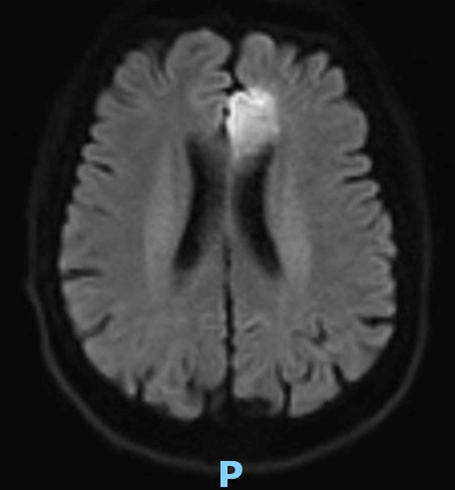

Le type d’hémianopsie est très important car il permet de localiser une atteinte neurologique, en connaissant le trajet des voies optiques.

Figure d’après le Collège des enseignants de neurologie (CEN). Altération aiguë de la vision.

Cette question supposait d’avoir bien en tête le schéma des voies optiques, et d’avoir des repères sur les principaux territoires vasculaires cérébraux et l’atteinte clinique associée. Il bien mentionné par le CEN que l’hémianopsie latérale homonyme gauche peut se voir dans un AVC sylvien superficiel droit.